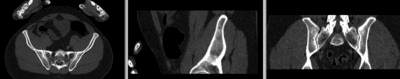

original unregistered unregistered

registered (affine) registered (affine)]

registered (nonrigid w/o masking) registered (nonrigid w/o masking)